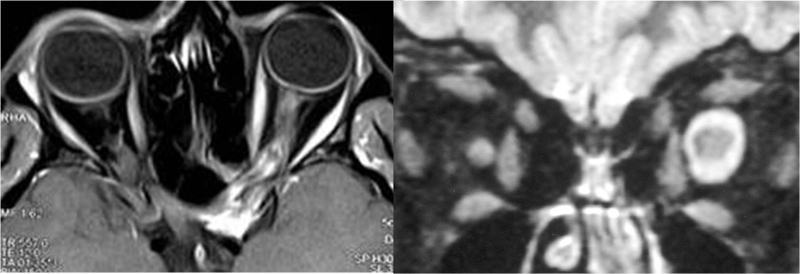

La presentación clínica de los tumores del nervio óptico es variada (atrofia papilar, edema de disco, síndrome quiasmático, pérdida visual o ambliopía, exoftalmos, alteraciones de la motilidad, pérdidas visuales transitorias…). En todos los casos las pruebas de neuroimagen orbitocraneal son cruciales en el diagnóstico y el seguimiento evolutivo. Habitualmente se trata de gliomas benignos del nervio óptico (sobre todo en infancia/adolescencia) o de meningiomas de la vaina del nervio óptico. Repasamos las características radiológicas principales de ambos (Figura 10):

Figura 10. Imágenes de RM: meningioma de la vaina del nervio óptico izquierdo (izquierda) y glioma de nervio óptico izquierdo (derecha)

-

Glioma del nervio óptico:

- La TC muestra un engrosamiento isodenso del nervio, con frecuencia fusiforme. Puede haber agrandamiento del canal óptico, de la silla turca, y también del quiasma y del nervio contralateral (aun sin afectación clínica).

- En RM el engrosamiento del nervio es iso- o hipointenso en T1 e isointenso en T2, excepto si existe gliomatosis aracnoidea periférica o degeneración quistica, que se presentará con hiperintensidad en T2. Puede presentar áreas de alta señal en T1 por degeneración mucinosa y el realce con el contraste es variable.

Meningioma:

- En TC, se aprecia un engrosamiento isodenso o hiperdenso tubular del nervio afecto. Puede haber calcificaciones en la forma psamomatosa.

- En RM, son isointensos tanto en T1 como en T2, y presentan un realce muy destacado tras la administración de contraste, a diferencia de los gliomas.